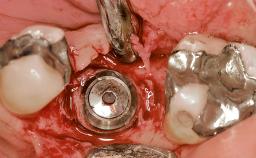

Early Placement of an Implant in a Maxillary Right Central Incisor Site

Type of Implants Two-Piece

Attachment Two-Piece

Bone Augmentation Horizontal|Simultaneous

Augmentation Materials Autogenous chips|Xenogenous|Membrane

Bone Volume Deficient horizontally, allowing simultaneous augumentation